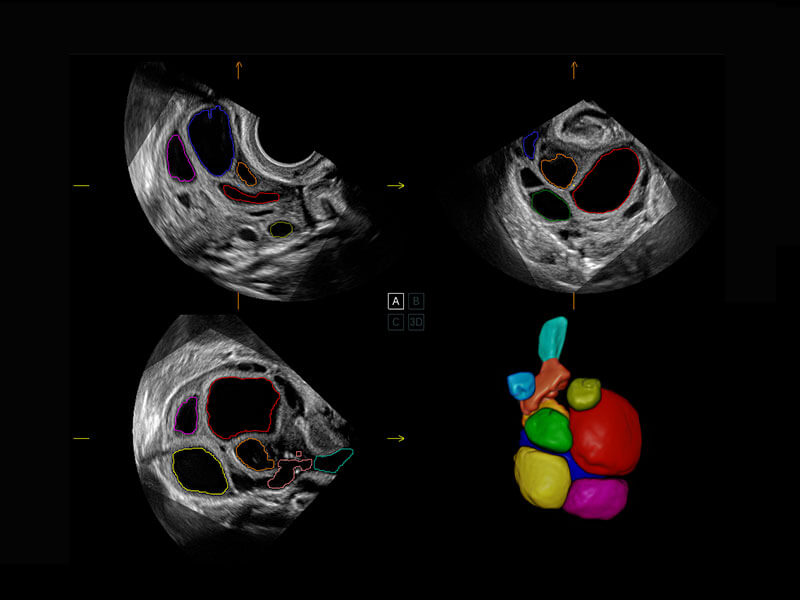

P60搭载一系列胎儿心脏成像技术,实现精细的胎儿心脏评估。

四腔切面

右室双出口

胎心容积成像